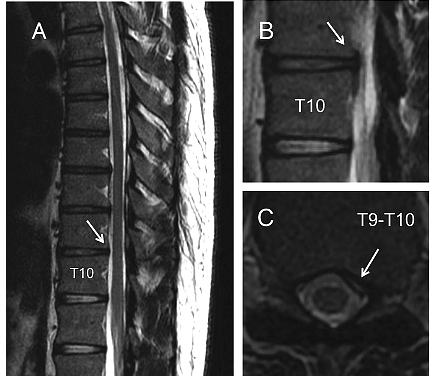

On physical examination by an orthopedic surgeon, the thoracic radicular pain was exacerbated by bending forward. Neurological examination revealed hypoesthesia of the left side of the chest at the level of the lower thoracic spine. Therefore, a possible thoracic disc herniation was suspected. This suspicion was confirmed by magnetic resonance imaging (MRI) of the thoracic spine, on which a left-sided paramedian disc herniation at the T9-T10 level was found (Figure 1).

Initial MRI (T2-weighted, sagittal (A), parasagittal (B) and transverse(C)) of the thoracic spine, one month after the onset, showing at the T9-T10 level, a disc protrusion on the left side that deforms the dural sac but not the medulla.